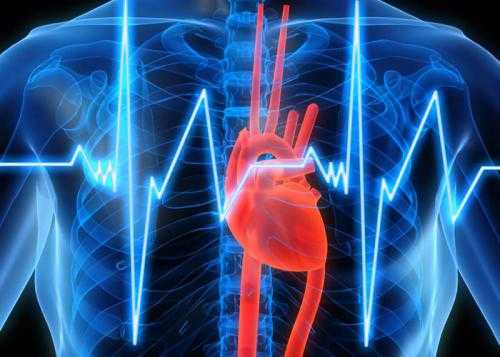

Медики раскрыли, почему сердечный приступ опасен даже для здоровых людей

Разрыв сердца обычно является смертельным для человека последствием перенесенного им инфаркта миокарда. Подобный разрыв может случиться и у тех, кто с виду здоров, – этому способствуют разные факторы.

Врачи разделяют внутренние, наружные и внешние разрывы сердца, но иногда случается полный разрыв сердца с повреждением по всей глубине, об этом пишет портал «Рамблер/доктор». Почему же сердце отказывает людям, которые не жалуются на здоровье?